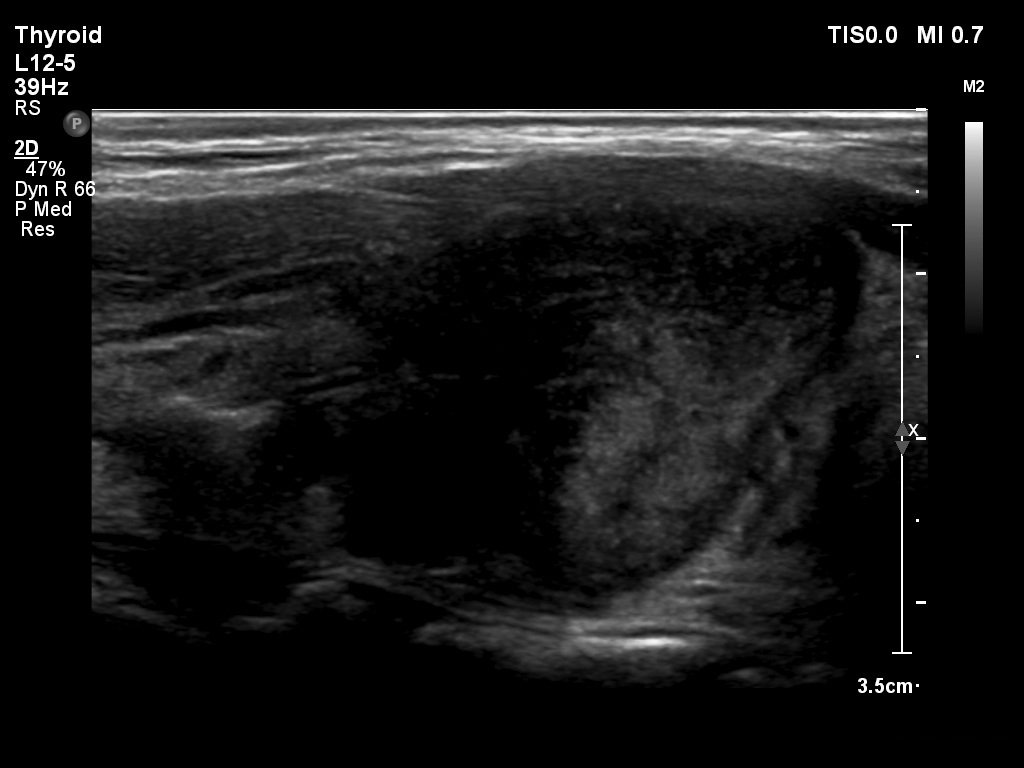

First examination (1st to 3rd rows of images):

Ultrasonography: Both lobes presented hypoechogenic ill-defined areas. The echogenicity index was 80% in the right lobe while 20% in the left thyroid. The vascularization was significantly decreased.

Elastography demonstrated hard areas according to the hypoechogenic field in the left lobe while almost the entire right lobe proved to be hard.Cytological diagnosis: subacute, granulomatous de Quervain's thyroiditis.